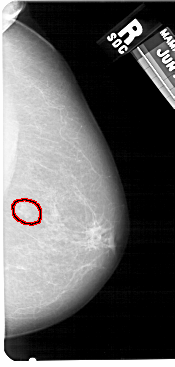

A_1428_1.LEFT_CC

RIGHT_CC LINES 5491 PIXELS_PER_LINE 2611 BITS_PER_PIXEL 12 RESOLUTION 43.5 OVERLAY

FILE: A_1428_1.RIGHT_CC.OVERLAY

TOTAL_ABNORMALITIES 1

ABNORMALITY 1

LESION_TYPE MASS SHAPE LOBULATED MARGINS ILL_DEFINED

ASSESSMENT 4

SUBTLETY 4

PATHOLOGY BENIGN

TOTAL_OUTLINES 1

BOUNDARY